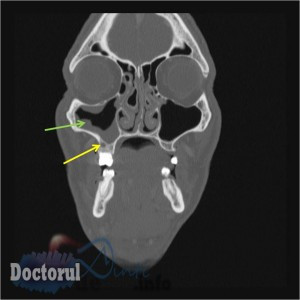

- - Factorii iatrogeni care cuprind obturarea radiculară în exces (materialul de obturaţie depăşind nivelul apexului şi pătrunzând în sinus), extracţia dentară cu deschiderea sinusului sau împingerea unui rest radicular în interior sau chiuretajul făcut într-o manieră agresivă.

- - Complicaţiile altor tratamente precum implantul dentar (alegerea greşită a dimensiunilor) sau sinus lifting-ul (tehnică incorectă).

- Endobucal: puroi la nivelul dintelui cauzal, durere în fosa canină, manevra Valsalva pozitivă. Pe lângă cele enumerate anterior mai putem adăuga şi stare generală alterată cu scăderea poftei de mâncare (inapetenţă) şi febră, iar examenul radiologic va evidenţia o discretă opacifiere unilaterală la nivelul sinusului maxilar.

- Endobucal: afecţiuni dento-parodontale, mucoasă îngroşată. Starea generală a organismului nu este afectată, iar examenul radiologic arată opacifiere periferică unilaterală a pereţilor sinusali.